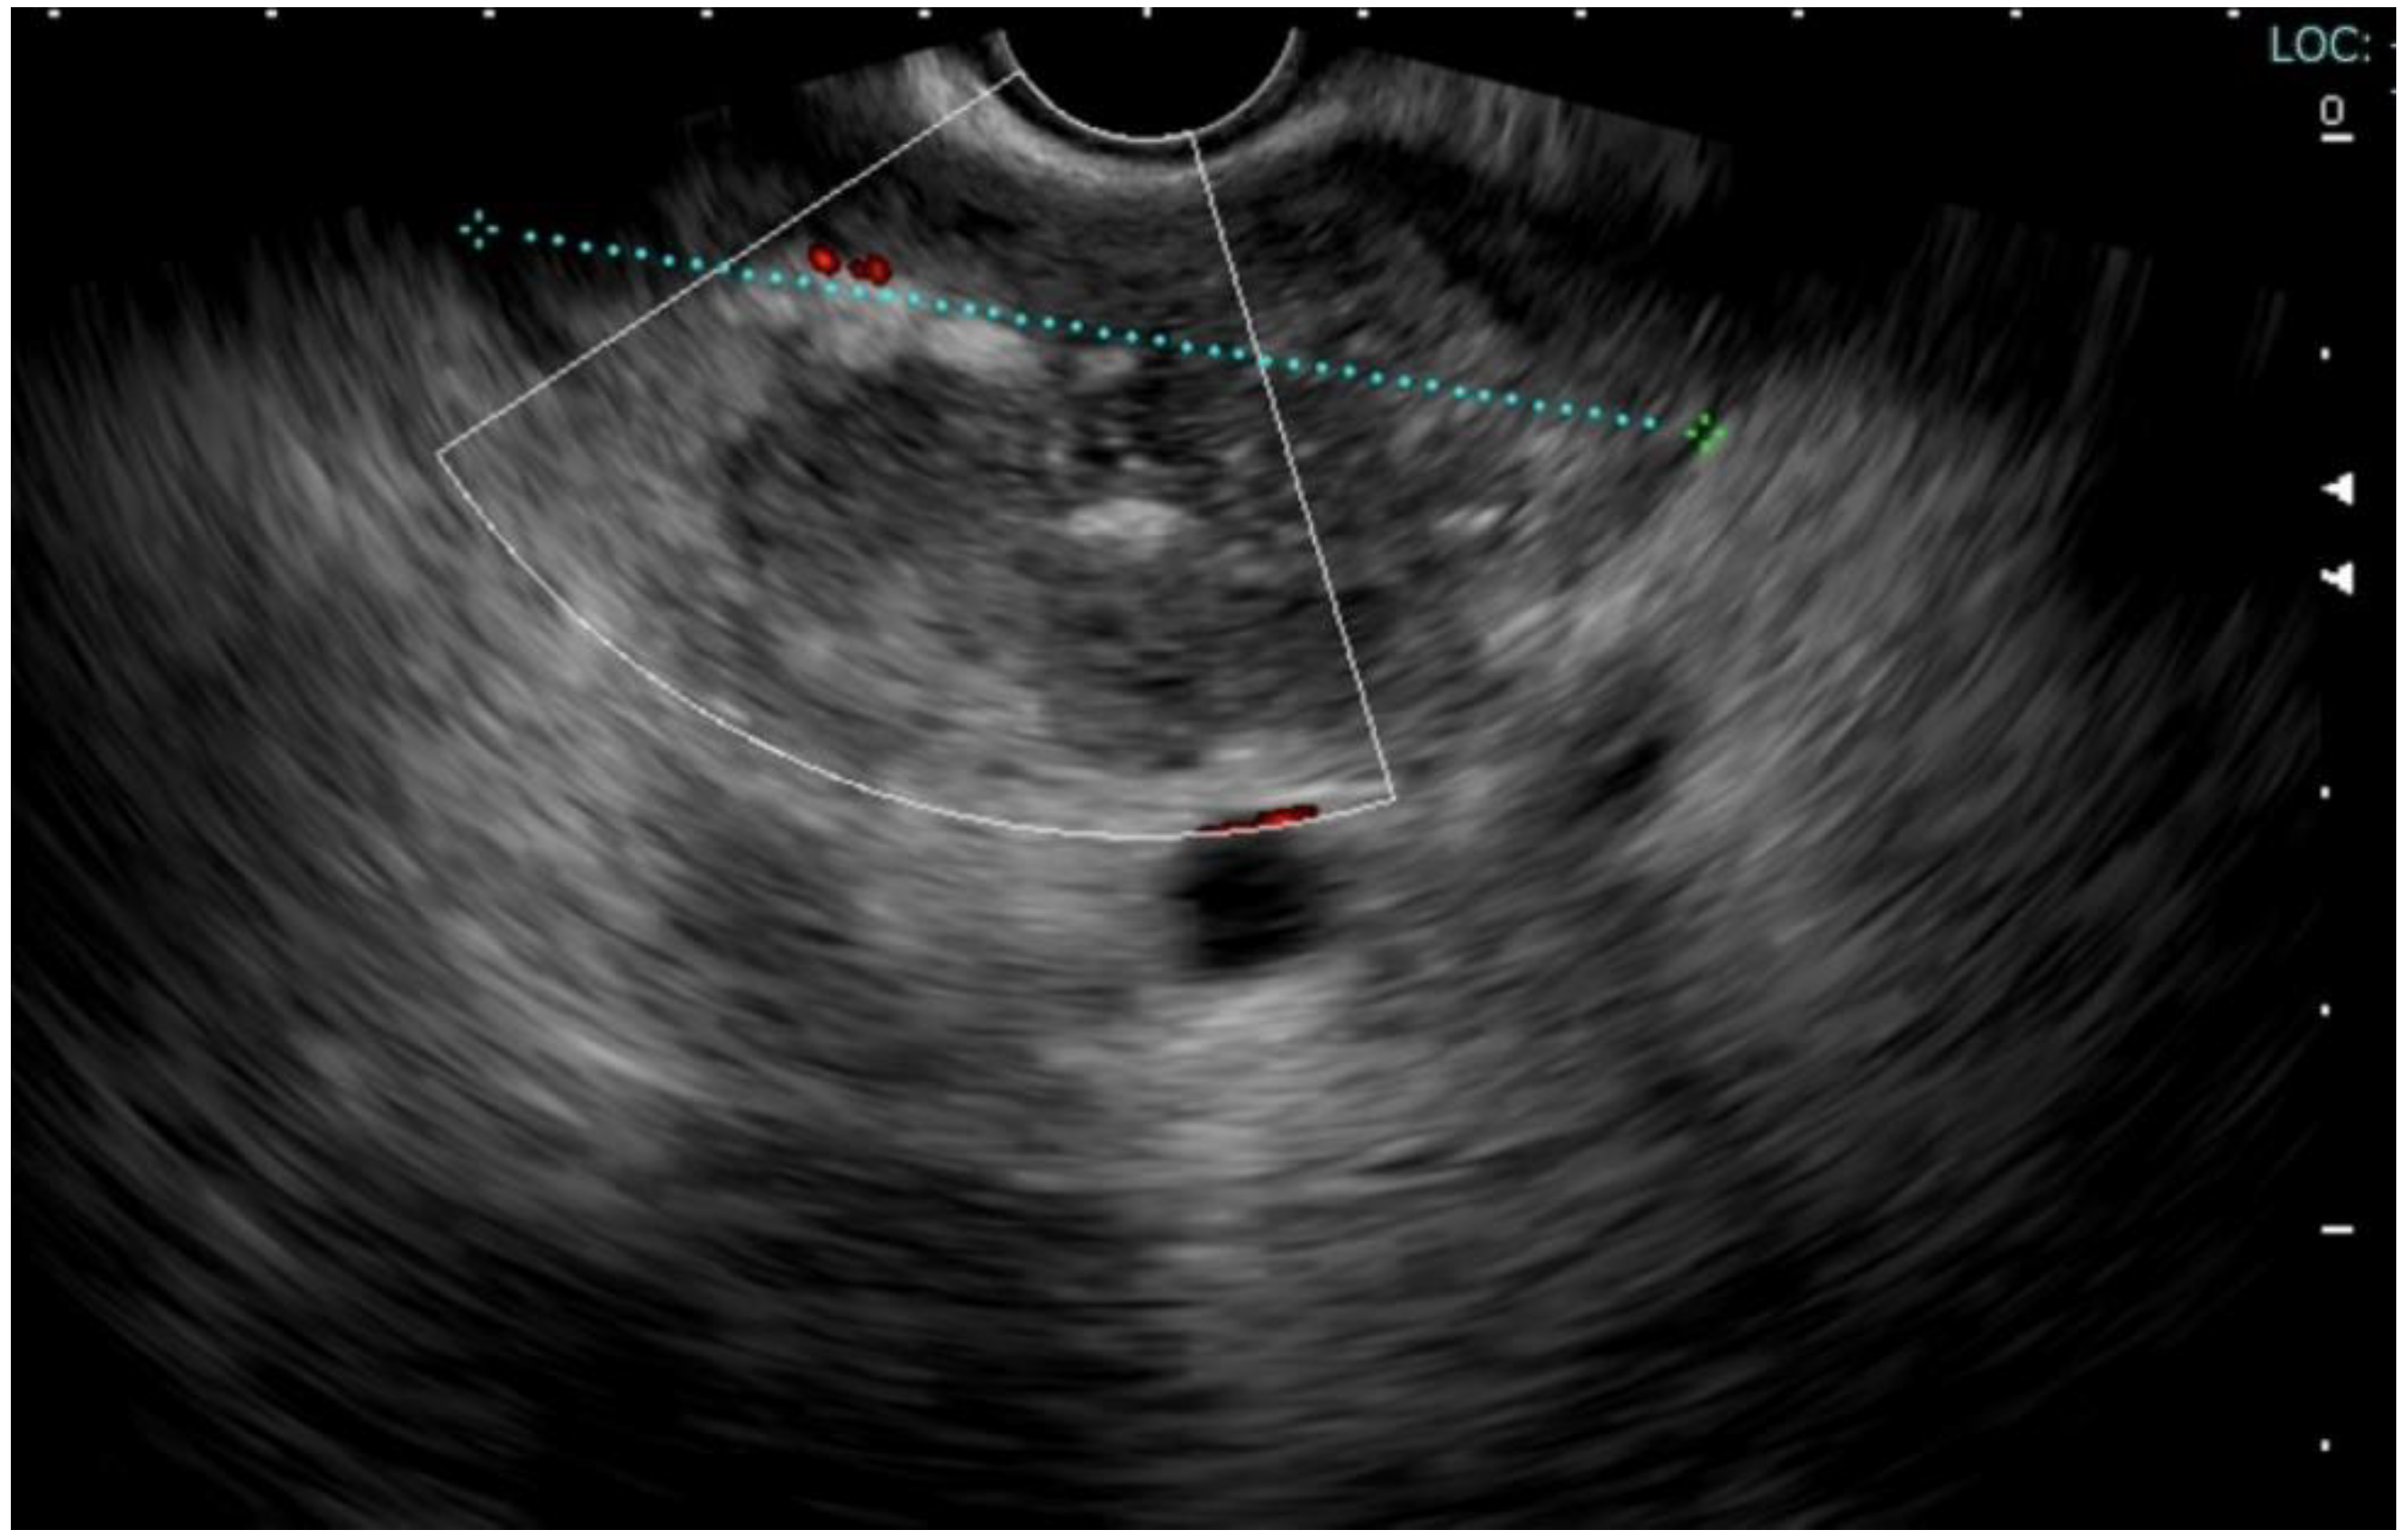

Approximately two months after the hospitalization, they returned to the hospital with epigastric pain and fever (38 °C). Laboratory results showed a WBC count of 14,530/mm3 (neutrophils: 78%) and a CRP level of 163 mg/L (<5 mg/L), procalcitonin 0.14 ng/mL. Pancreatic enzymes and liver function test results were within the normal ranges. An abdominal CT scan showed the presence of multiple confluent fluid collections extending from the head to the tail along the entire pancreatic profile containing air (Figure 1). An endoscopic investigation and an endoscopic ultrasound (EUS) were performed. The upper endoscopy revealed the presence of a fistula opening of about 8 mm in diameter in the duodenum bulb with leakage of purulent material (Figure 2). EUS showed the presence of air in the fistula and a complex 5 cm fluid collection in the tail of the pancreas (Figure 3). An abdominal CT scan with gastrografin confirmed the fistulous channel originating from the first duodenal portion, which gives rise to two branches, anteriorly in the head of the pancreas and posteriorly in the tail. After a collegial reunion with clinicians, surgeons, radiologists, and gastroenterologists, it was decided to proceed with the drainage of the larger pancreatic collection in an attempt to heal the fistula with the duodenum. EUS-guided trans gastric drainage of the fluid collection was performed using a 16 × 20 mm lumen-apposing metal stent (LAMS, Hot-Spaxus, Taewoong Medical Co., Gimpo, Korea), obtaining drainage of copious purulent material in the stomach (Figure 4).

Figure 4.

EUS-guided trans-gastric drainage of the fluid collection using a 16 × 20 mm lumen-apposing metal stent (LAMS, Hot-Spaxus, Taewoong Medical Co, Gimpo, Korea).